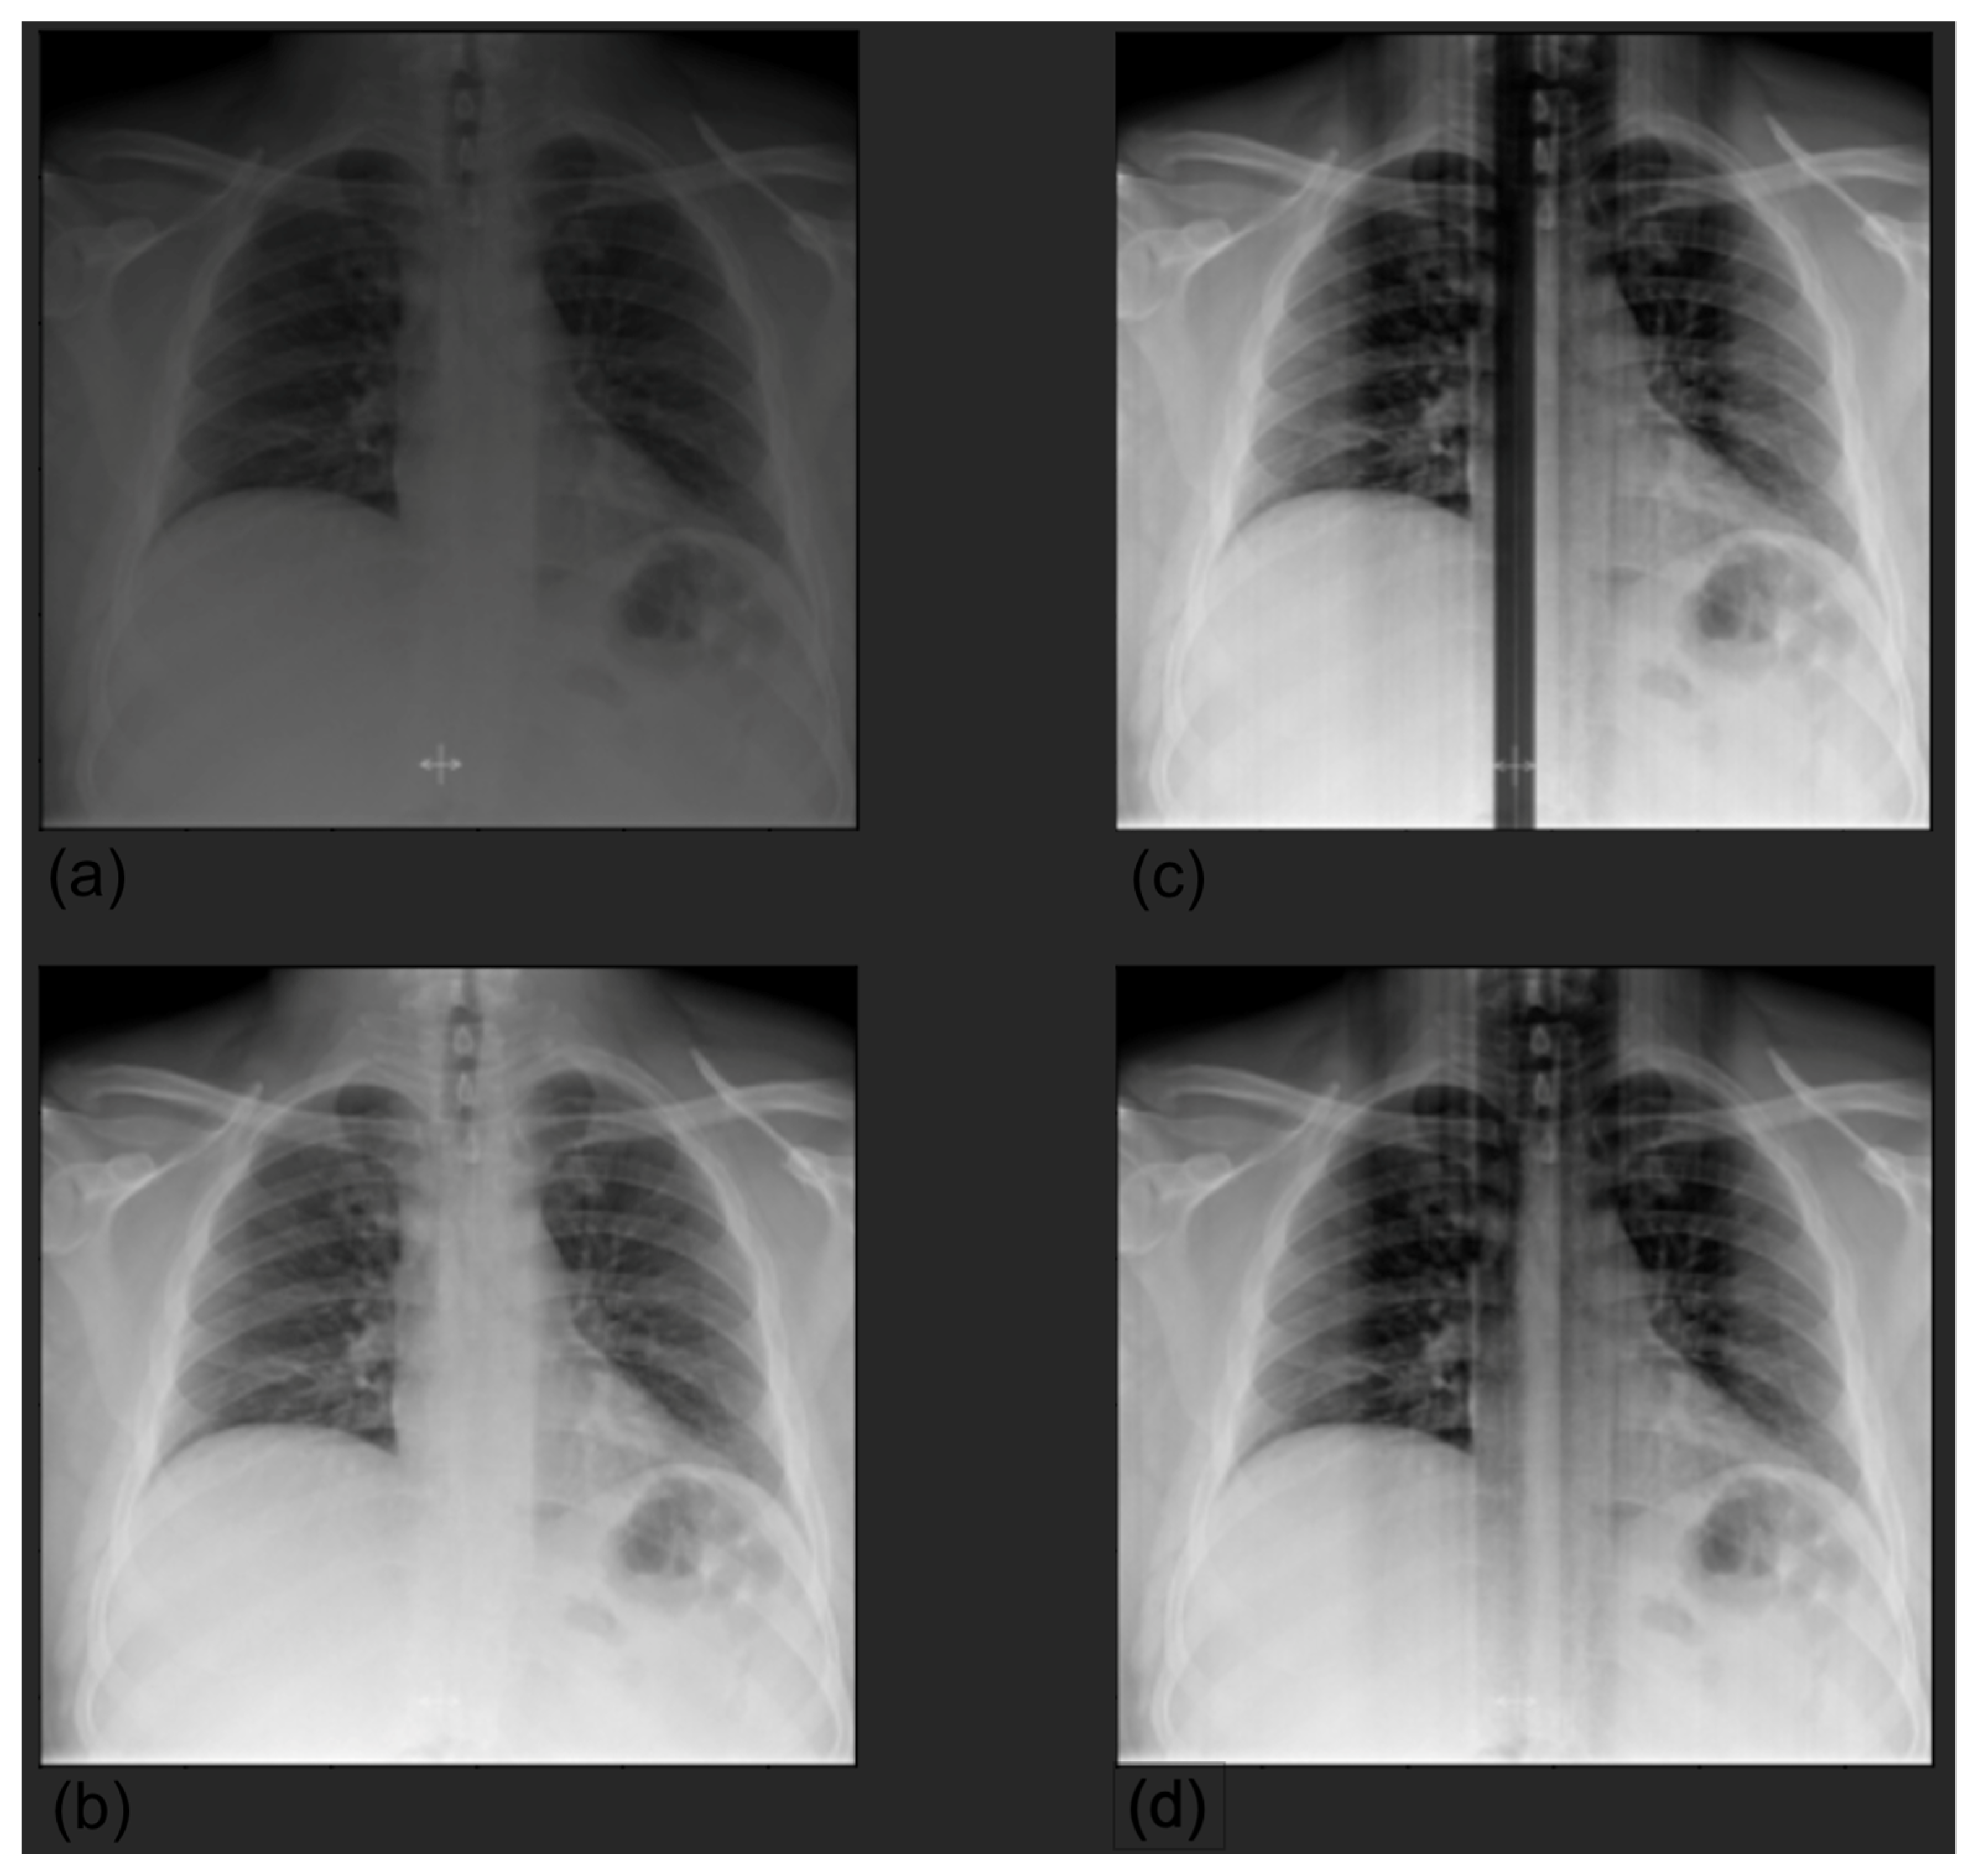

Preprocessing. For both datasets, we selected only anteroposterior images. Concerning CheXpert, following the approach described in [15], we resized the images to 256 × 256, and a chest region of 224 × 224 was extracted using a template-matching algorithm. We then normalized the images by scaling their values in the range [0, 1]; because the original models were pretrained on ImageNet, we further standardized them with respect to ImageNet mean and standard deviation. Concerning HUM-CXR, we selected X-rays acquired with an anteroposterior view, screening the images according to the series description in DICOM format, which had to be anteroposterior, posteroanterior, or portable; the final sample comprised 941 image of 746 patients. First, we clipped pixel values with a maximum threshold of 0.9995 quantile to minimize the noise due to the landmark (see Figure 1).

Figure 1.

Preprocessing by clipping values larger than the 0.9995 quantile. The presence of a landmark, significantly whiter than the other pixels, created significant noise after normalization (a); original image (b); clipped image (c); normalized original image (d). To match the input dimension of the models, we resized the images to 224 × 224 and encoded them as RGB images by repeating the images for three channels. This was a necessary step in order to use the state-of-the-art image classification networks already pretrained on the ImageNet dataset. Then, we normalized each image by scaling the values in the range.